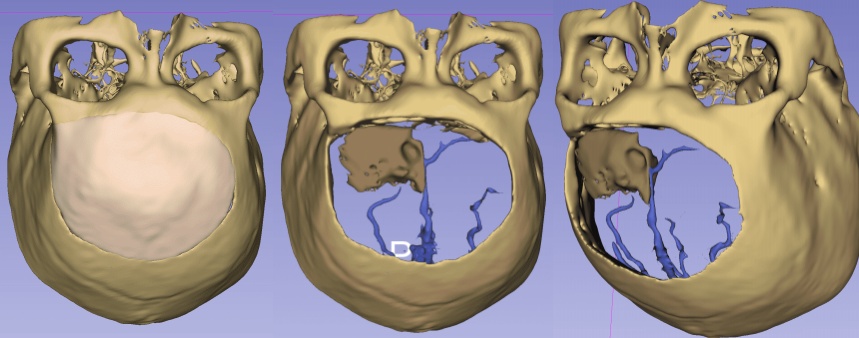

影像重建

腫瘤與靜脈、矢狀竇的關系

靜脈影像重建

CT重建

左額內外板可見骨質增生